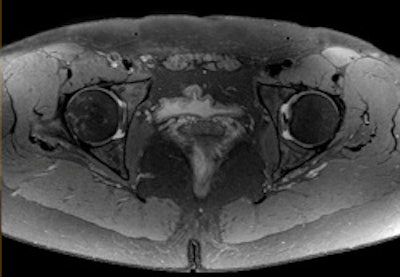

Left: PET tracer uptake in the liver can be combined with the time-varying enhancement of dynamic MR scans to visualize hepatic tumor characteristics. Right: MR and PET come together to support tumor staging. In this case, high-resolution MR provides a clear image of the pathology within the pelvic structure, while PET displays the hypermetabolism component of the lesion. Images courtesy of Siemens.Drzezga believes that combining the two modalities offers a number of clinical advantages, not least in eliminating the need for separate diagnostic examinations. Furthermore, the exact anatomical registration of structural and functional/molecular information may improve allocation of suspect findings and improve image quality, for example by motion correction of regions of the body that do not remain rigid during examination. The Munich team will also be exploring how the performance of PET/MR compares with that of PET/CT. There is some evidence that the superior soft-tissue contrast achievable with the newer system will offer significant benefits, even before physicians consider the safety issues involved with any radiation-based imaging technology such as PET/CT, Drzezga suggested.

High-resolution MR image of the hip with spectral attenuated inversion-recovery (SPAIR) fat suppression. Image courtesy of Philips.